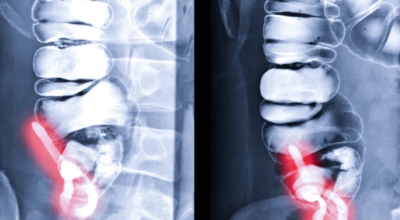

맹장염의 정확한 원인은 항상 명확하지는 않습니다. 하지만 충수가 막히거나 감염되었을 때 나타나는 것으로 여겨져요. 막힘은 다음등의 여러가지 요인으로 기인해서 일어날 수 있어요.

배설물: 맹장에 배설물이 축적되면 막힘을 일으켜 염증을 유발할 수 있어요. 확대된 림프성 여포: 충수에는 면역 체계의 일부인 림프성 여포가 포함되어 있어요. 이 모낭이 커지면 맹장을 막고 염증을 나타나게 할 수 있어요. 순수하지 않은 물질: 때로는 삼킨 껌 조각이나 씨앗등의 찌꺼기이 맹장에 달라붙어 염증을 유발할 수 있습니다. 종양: 드물게 충수돌기에서 종양이 발생해서 염증을 유발할 수 있어요.